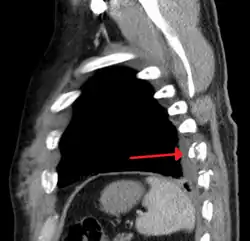

Right sided pneumothorax and rib fractures -

Two broken ribs as seen on parasagittal CT